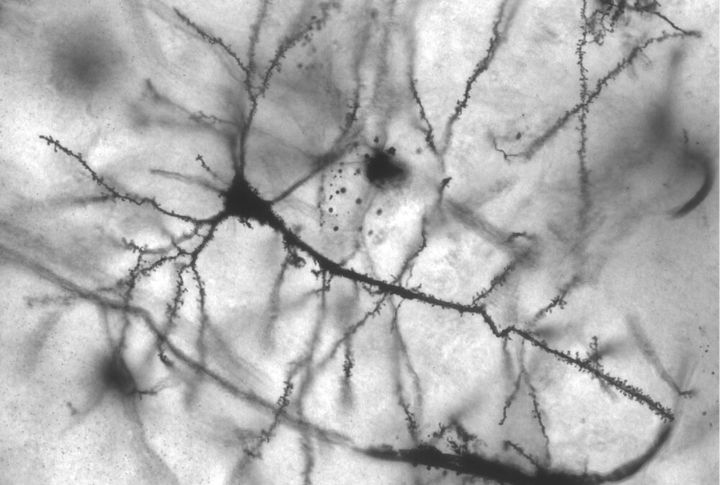

Brain Cells May Struggle To Function

Neurons are like messengers, constantly firing signals to keep your body running smoothly. But what happens when plastic gets in the way? Microplastics can interfere with cellular communication, potentially slowing processing speed and reaction time. Experiments on animal models show that prolonged exposure to nanoplastics alters neural activity and weakens synaptic connections.